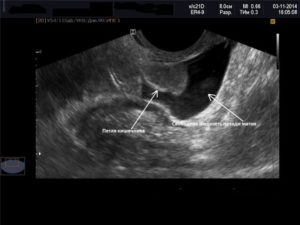

Жидкость в позадиматочном пространстве при беременности обнаруживается только в том случае, если оплодотворенная яйцеклетка прикрепилась в неположенном месте, то есть при внематочной беременности.

Это неизбежно приведет к разрыву стенки маточной трубы, из-за чего жидкость и проникнет за матку.

Но «неправильное» зачатие обычно обнаруживается (по боли, ухудшению самочувствия, мажущим выделениям) задолго до того, как накопится излишняя жидкость.

Патологическое скопление крови может быть спровоцировано разрывом маточной трубы в результате внематочной беременности. Разрыв обусловлен ростом плода в нетипичном для него месте. Такое случается при непроходимости труб или нарушения их сократительной способности.

Чтобы вовремя диагностировать аномальное расположение эмбриона, требуется посетить кабинет УЗИ и проанализировать динамику гормона ХГЧ (Подробнее о ХГЧ здесь) . Согласно статистическим данным, чаще всего патологическую беременность диагностируют до момента разрыва трубы.

После обнаружения крови в Дуглассовом пространстве потребуется хирургическое вмешательство. Первоначально принимаются меры по откачиванию крови. Следующим шагом устраняется очаг проблемы. При внематочной беременности удаляют часть маточных труб.